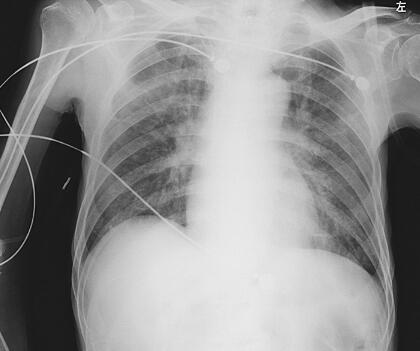

辅助检查:血常规:WBC 10.7×109/L,Hb 109g/L,N 83.8%,PLT 88×109/L;血气分析:pH 7.46,二氧化碳分压24.7mmHg,氧分压95mmHg,BE −6.3mmol/L,碳酸氢根17.7mmol/L;生化全项:TP 48.9g/L,ALB 24.7g/L,PA 0.09g/L,Na+ 156mmol/L,Cl− 124.7mmol/L,CO2 21.4mmol/L,BUN 10.62mmol/L,Ca2+ 1.92mmol/L,血磷0.71mmol/L,CHO 2.44mmol/L,LDH 355U/L,HDL 0.52mmol/L,LDL 1.23mmol/L,CRP 141.21mg/L。BNP 9219ng/L。尿常规:尿潜血(++),尿白细胞(+++),镜检红细胞2~3个/HP,镜检白细胞满视野。胸片(6月18日):考虑肺水肿,不除外合并感染。

图1 2011年6月19日胸片